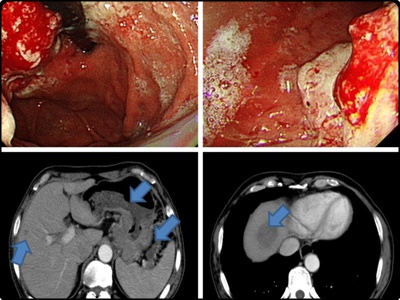

위암 4기 생존율

위암 4기 판정을 받았다고 한다면 이는 임파선과 원격 전이가 진행된 것으로 봐야합니다. 이런 상황이 되면 암세포가 혈액이나 림프액을 통해 전신에 퍼졌다는 것을 의미하기도 합니다. 때문에 항암 치료와 예후가 중요한 시기이기도 합니다.

위에서 위암 초기증상은 포함하여 빈혈, 호흡관란, 황달 및 복수, 골절 및 골통 그리고 신장 기능의 저하로 인한 소변량이 감소하게 됩니다.

그리고 위암 4기 생존율은 환자의 상태와 치료 방법에 따라 많은 차이가 있습니다. 특히 수술 치료 후 재발이 되지 않는다면 생존율은 더 높아집니다. 수술치료, 방사선 치료, 항암 치료, 면역 치료 등의 다양한 치료법이 있기 때문에 꾸준히 치료와 관리를 병행하게 되면 생존율을 높일 수 있습니다.